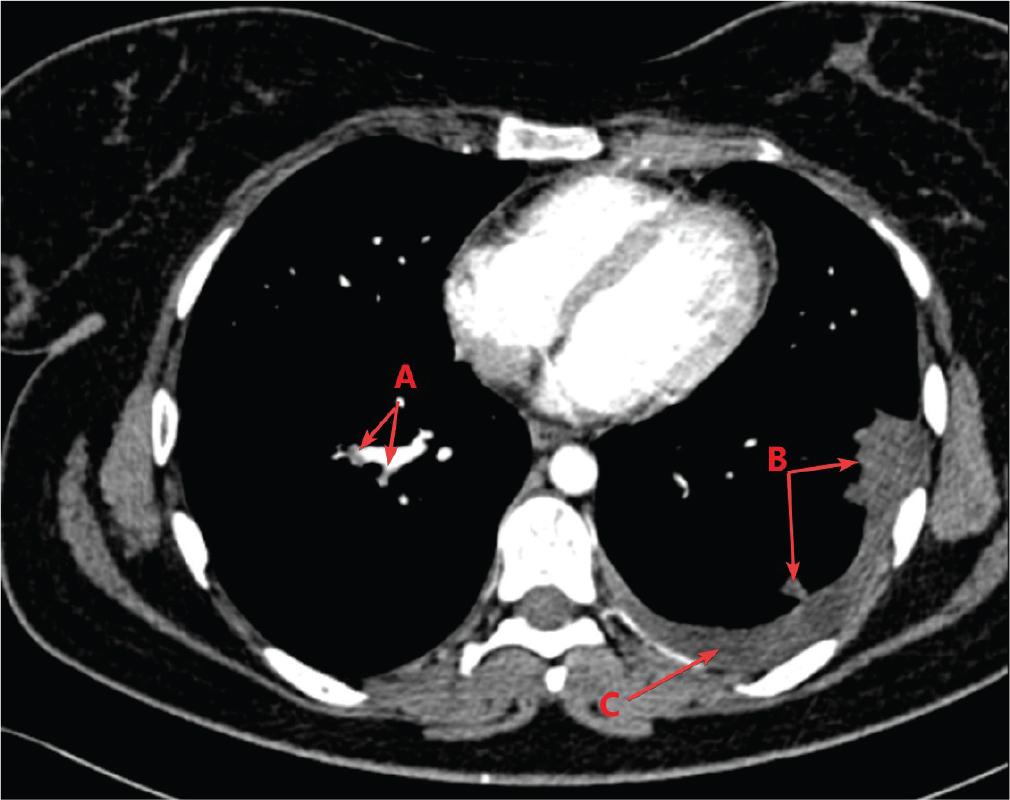

Patient B, a 22-year-old non-smoker with a 5-month history of COC use for hirsutism and dysmenorrhoea, presented with progressive exertional dyspnoea and posterior chest pain aggravated by movement and deep inspiration, symptoms that had been present for approximately 1 month. These symptoms prompted a referral to another medical facility, where she was diagnosed with pneumonia and treated with broad-spectrum antibiotics, but without significant improvement. Physical examination revealed an SpO2 of 96%, tachycardia of 100 bpm and normal blood pressure (115/75 mmHg). According to the revised Geneva score, the patient was classified as having an intermediate clinical probability of PE (4). Blood tests indicated a mildly low haemoglobin (11.1 g/dL), an inflammatory syndrome (CRP = 38.65 mg/L) and elevated D-dimers (715 ng/mL). The ECG showed inverted T waves in V1–V3, and echocardiography revealed moderate tricuspid regurgitation, moderate PH and sPAP of 44 mmHg. Chest CT confirmed PE in the bilateral subsegmental arteries, with bilateral pulmonary infarcts and bilateral pleural effusion (Figure 3). Based on the clinical and paraclinical findings, the patient was diagnosed with low-risk PE, in accordance with current risk stratification guidelines (4). Anticoagulation treatment was initially administered with enoxaparin 0.8 mL s.c. every 12 hr for 5 days, followed by apixaban 10 mg twice daily for 7 days, and subsequently continued with a maintenance dose of 5 mg twice daily, according to international recommendations (5), with good clinical evolution. COC therapy was discontinued. The patient was discharged on the seventh day of hospitalisation with the recommendation to continue oral anticoagulation with apixaban. Haematology consultation revealed the presence of a heterozygous factor V Leiden mutation, and anticoagulant treatment was discontinued after 6 months, in accordance with haematological guidelines (6).

Contrast-enhanced chest CT scan: (A) PE, (B) pulmonary infarcts, (C) pleural effusion. CT, computed tomography; PE, pulmonary thromboembolism.